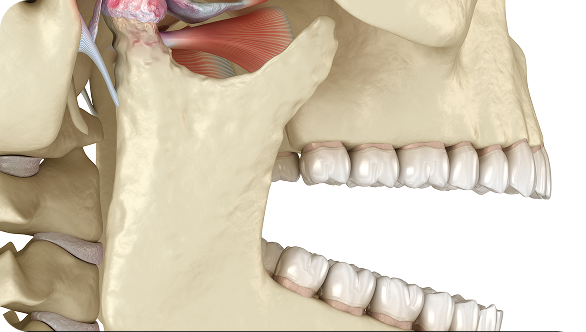

- 대한턱관절교합학회 정회원, 인정의

- 아시아 턱관절연수회 수료

- Orthognathic surgery in skeletal Class III long face with severe facial asymmetry and temporomandibular disorder(TMD) 2nd Taiwan International

Orthodontic Meeting, 2018, Poster - Changes in condylar position after 2-jaw surgery-first orthognathic surgery in a skeletal Class III patient with facial asymmetry Surgery First Summit,